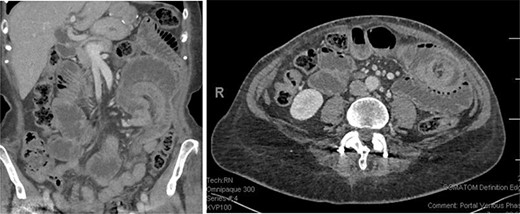

A 72-year-old female presented to the emergency department with 12 h of severe abdominal pain. She had previously undergone a LRYGBP 3 years earlier resulting in 60 kg of weight loss. On further questioning, the patient reported that she had complete obstipation for 24 h. Computerized tomography (CT) scan demonstrated a jejunal intussusception at the site of the jejunojejunal anastomosis (Fig. 1).

On the left coronal reconstruction showing the area of intussusception (top right); on the right an axial reconstruction showing the classical target sign suggesting intussusception (top right).